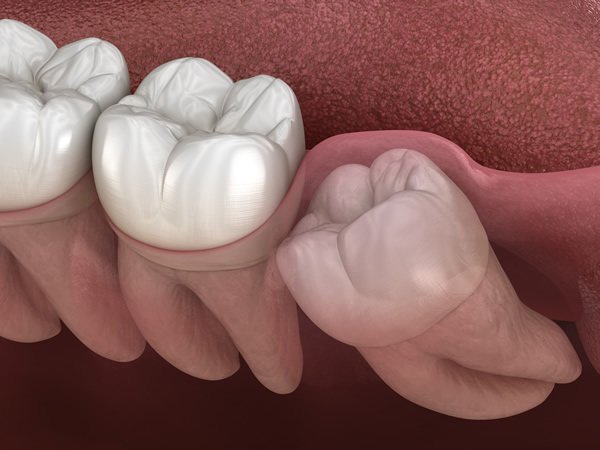

親知らずを抜くべきかどうかの判断は、その生え方によって大きく左右されます。斜めに生えていたり、正しい方向に伸びていない親知らずは、周囲の歯に悪影響を及ぼしたり、清掃が不十分になって虫歯を招きやすいため、抜歯をおすすめすることが多いです。

親知らずは生え方によって、比較的容易に処置できる場合もあれば、慎重な対応が求められる場合もあります。特に

- 親知らずが斜めに生えたり、部分的にしか出ていない場合、隣接する歯に圧力をかけることがあります。また、炎症や腫れを引き起こす恐れもあるため、抜歯を検討するケースが多いです。歯科医師がレントゲン検査などを通じて判断し、適切な処置を行います。

- 親知らずが横や斜めに生えている場合、歯並びに影響を及ぼす可能性があります。